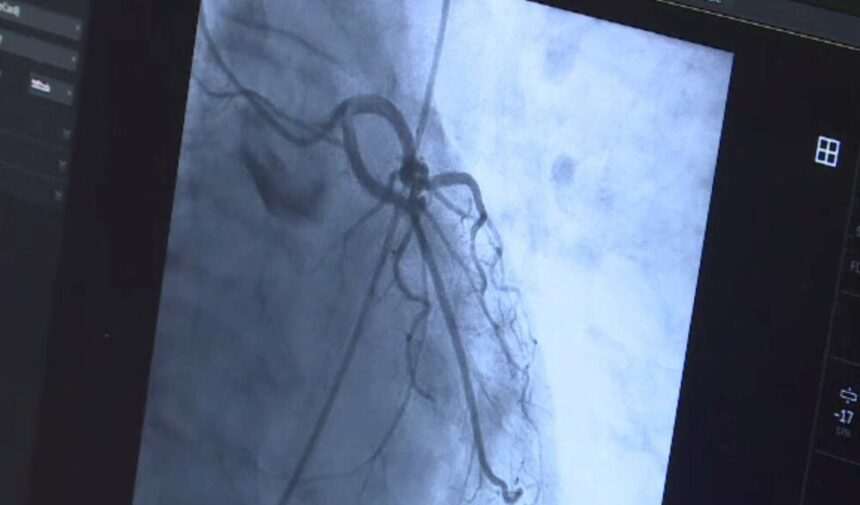

Prin vena femurală, au introdus un cateter cu care a ajuns în inimă, iar de aici în artera pulmonară, pe unde sângele neoxigenat ajunge în plămâni. Prin acel cateter a fost introdus iniţial un stent în artera pulmonară apoi şi valva pulmonară – dispozitivul care va preveni reîntoarcerea sângelui înapoi în inimă.